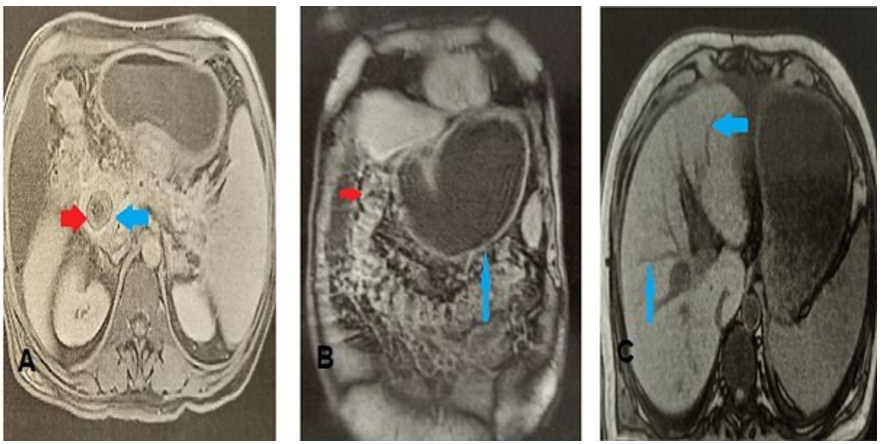

Abdominal magnetic resonance imaging (MRI) revealed an enclaved gallstone of three centimeters in the second duodenum (shown in Fig. 2A), gastric distension (shown in Fig. 2B), cholecystoduodenal fistula, and pneumobilia (shown in Fig. 2C).

Figure 2: MRI images (A) Axial MRI slide, sequence T2, at the portal phase, showing the stone enclaved in the second duodenum(B) Coronal section of abdominal MRI T2 sequence showing gastric distension upstream of the calculus. (C) In-phase abdominal axial slide showing pneumobilia